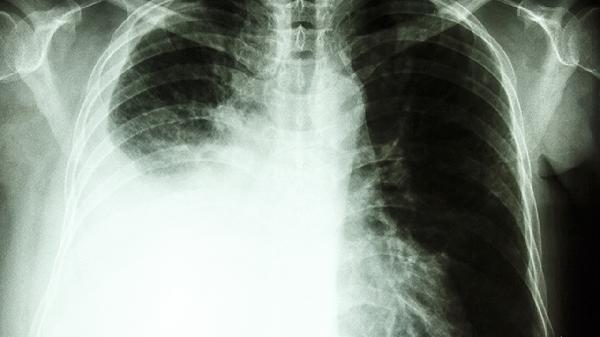

2、活检结果可能显示多种情况。除了癌症,活检还可能发现良性肿瘤、炎症、感染、自身免疫性疾病等。例如,乳腺活检可能显示纤维腺瘤或乳腺炎,而非乳腺癌。肺部活检可能显示肺结核或肺炎,而非肺癌。活检结果的多样性意味着它并不仅仅用于癌症诊断。